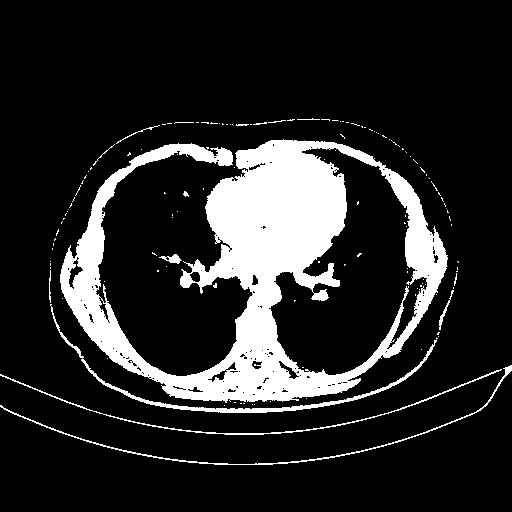

Slice 70 Targeting Evaluation

Patient ID: BM26032018

Model: cytran

Slice: Slice_70

Slice Thickness: 2.0mm

Conversion: NATIVE β VENOUS

4Γ3 grid: Rows show different image types (Original NATIVE, Reconstructed NATIVE, Original VENOUS, Generated VENOUS), Columns show windowing techniques (No Window, Lung Window, Mediastinum Window)